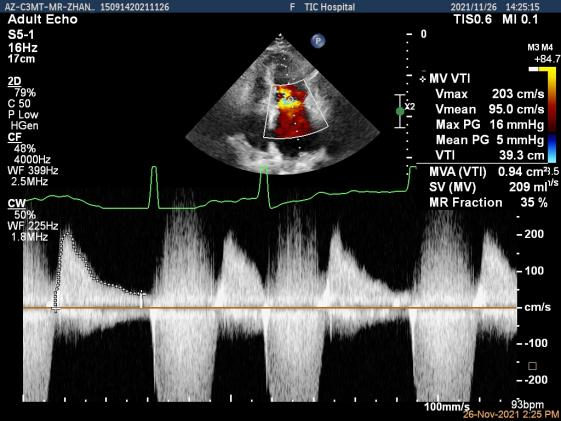

Qlab软件勾画估测瓣口面积约:4.42cm²

二尖瓣口平均跨瓣压差:5mmHg

第一个夹子放置侯二尖瓣口平均跨瓣压差:4mmHg

肺静脉血流频谱恢复正向

3.、本例患者二尖瓣瓣口面积临界范围,在钳夹后我们按照规范步骤,确认二尖瓣跨瓣压差、瓣叶钳夹长度和肺静脉血流频谱改善均达到满意效果后放心释放器械,术后患者的血流动力学和临床症状迅速改善。因此,要做好不简单的病例,基石就是把每一个简单的步骤规范做好。随着我们TEER治疗经验的积累,相信不久的将来,一套标准的中国TEER临床路径将会应运而生,推动整个领域的迅速规范发展。